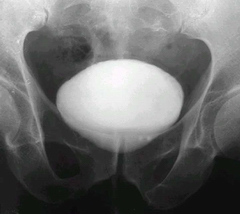

老人較容易得膀胱結(jié)石的原因? 膀胱結(jié)石患者比較多,對于膀胱結(jié)石的病因,老年人了解的很少,研究表明,老年人得膀胱結(jié)石的幾率更大,是什么原因?qū)е铝诉@種情況呢?齊齊哈爾?現(xiàn)代醫(yī)院專家為大家介紹。

齊齊哈爾?現(xiàn)代醫(yī)院專家指出,膀胱結(jié)石患者患上膀胱結(jié)石的原因是很多的a、可能是由上泌尿道結(jié)石掉下來的,最后形成膀胱結(jié)石。

c、可能是原發(fā)性的結(jié)石。

d、有些中老年人膀胱內(nèi)有異物而引起膀胱結(jié)石。